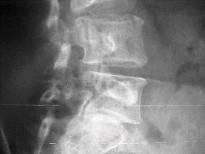

男,50岁,腰背痛,请结合图像,选出最可能的诊断 ( )A、L椎弓峡部不连及L滑脱B、L~S椎间盘突出C、L隐性脊椎裂D、移行椎E...